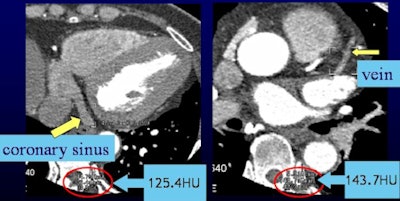

The study team measured attenuation at regions of interest in the ascending and descending aorta, left and right coronary arteries, and coronary sinus.

CT values in the coronary sinus were 112.7, 93.7, and 81.2 HU for Groups A, B, and C, respectively (p < 0.001). CT values within the ascending and descending aorta and the coronary arteries were higher than 300 HU in all three contrast groups.